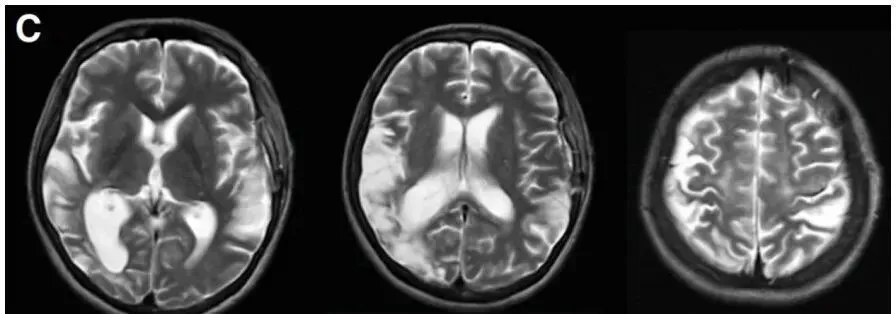

术后23天MR复查显示未出现新的缺血性或出血性病变,恢复良好。